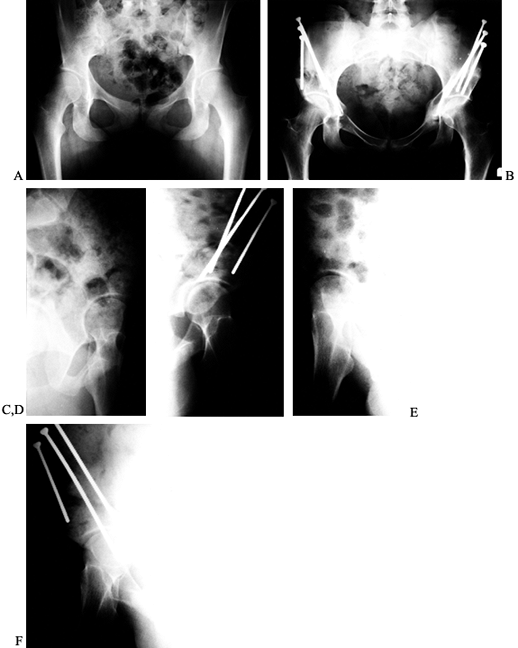

abduction radiographs (31,89,136,). Figure 104.4

shows a 17-year-old patient with bilateral dysplasia and arthritis who

underwent a combined Chiari and valgus–extension ITO on the left. At

over 3 years this hip has no pain or limp.

Figure 104.4. Chiari osteotomy combined with a valgus ITO. Preoperative AP view of the left hip (A) and false-profile view (B)

in a 17-year-old girl with bilateral hip dysplasia, arthritis, and leg-length inequality. Postoperative AP view of the pelvis (C) and false-profile view of the left hip (D) after Chiari osteotomy with simultaneous extension ITO and femoral shortening of 3 cm. AP view of the pelvis (E) and false-profile view (F) 3 years after surgery. The patient had no left hip pain and no Trendelenberg sign, but she elected for total hip replacement on the contralateral hip within the next year. |